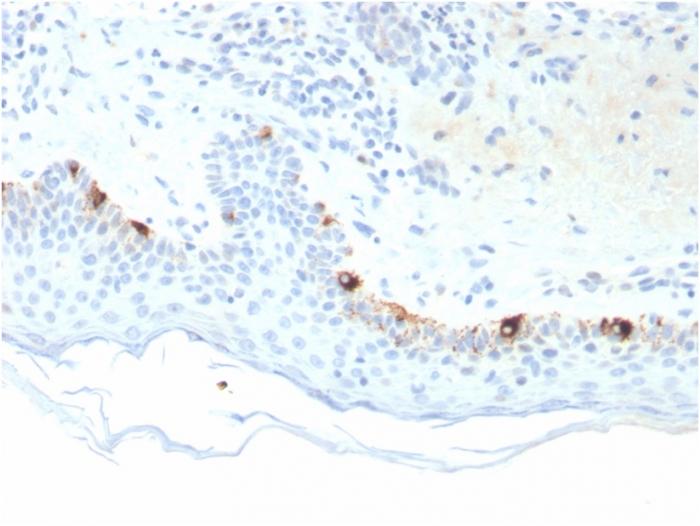

Reacts with a 75 kDa melanocyte-specific gene product, identified as Tyrosinase-related protein-1 (TRP-1). It is involved in melanin synthesis. TRP1 is present on the melanosomal membranes of melanoma, normal melanocytes and nevi. Recent evidence suggests that TRP-1 is involved in maintaining stability of tyrosinase protein and modulating its catalytic activity. TRP-1 is also involved in maintenance of melanosome ultrastructure and affects melanocyte proliferation and cell death. Primary antibodies are available purified, or with a selection of fluorescent CF® Dyes and other labels. CF® Dyes offer exceptional brightness and photostability. Note: Conjugates of blue fluorescent dyes like CF®405S and CF®405M are not recommended for detecting low abundance targets, because blue dyes have lower fluorescence and can give higher non-specific background than other dye colors.

Positive Control

SK-MEL-23, SK-MEL-19, SK-MEL-30, SK-MEL-37 cells. Human Skin or Melanoma.

Antibody target cellular localization

Vesicular

Cell tissue expression

Melanocytes

Tumor expression

Melanoma

IHC, FFPE (verified)

IHC (FFPE) (verified)